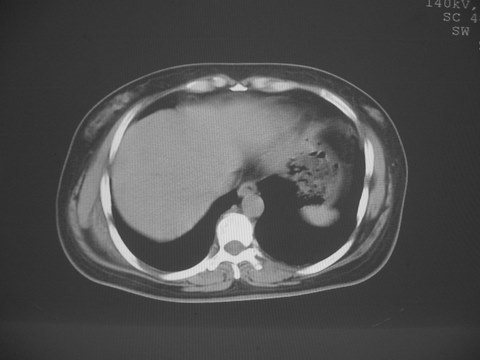

无意中发现右背部肩胛下缘半球状突起,无红,热,痛感觉。拍平片未见异常。ct发现右肩胛下角深层新月型软组织肿胀,ct值-50至15,大家看看是什么性质,来源,初步考虑来源于下后锯肿,考虑下后锯肌肿胀,可是病人无明确外伤史,也不疼痛

典型的弹性纤维瘤,从部位\\形态\\密度来看均极典型.现引用lzdyjg老师的点评:

一、弹性纤维瘤临床

是一种罕见的良性结缔组织病变,大多数学者认为是肩胛下角和胸壁之间的机械摩擦引起,是异常弹性组织发生的反应性的肿瘤样增生.82-99%的弹性纤维瘤位于肩胛骨下角附近的深部软组织内,也可发生于胸壁,肘部\\颈部\\髋部大腿\\足部\\坐骨结节\\股骨大转子附近.

本病几乎均为55岁以上老年人,女性显著多于男性,以从事繁重的手工劳动者为多见,1/3有家族史,病变多发于右侧.

二、弹性纤维瘤病理

常常呈边界不清橡胶样的灰白色纤维组织其间有小区域的黄色脂肪。肿块大小在2cm至15cm不等。由含有细胞数少的胶原组织和大量弹性纤维及少量粘液样基质和其间成熟的脂肪细胞构成。弹性纤维粗大、强嗜碱性、散在呈线形排列成小球形状成锯齿盘状,后者似串珠。弹性染色大分支或无分支纤维见致密的核及不规则锯齿样边缘。虽然弹性蛋白样物质可由胰弹性蛋白酶预先处理,但较皮肤控制的更难以消化。

三、弹性纤维瘤影像

典型位于背部,在肩胛下角和胸壁软组织之间,肿瘤表面为菱形肌和背阔肌所被覆深部,紧邻肋骨和肋间肌,呈半圆形或扁豆状,宽基底与胸壁相交,边界比较清楚,相邻的肌肉和肋骨无侵蚀,部分病变与其表面的临近肌肉之间可受压呈弧形的脂肪界面,肿瘤周围软组织无水肿。

在se序列上,可呈不均匀性改变,典型病变主要由浓密的结缔组织组成,t1wi、t2wi均与骨骼肌肉信号相似,病变内有散在的脂肪组织,呈线形或曲线形,信号为脂肪信号改变,stir可抑制。病变内可有囊变,t1wi呈低信号,t2wi呈高信号。

从mr表现可以推断ct影像,即肿块呈软组织密度,病灶内可出现脂肪密度的低密度影。